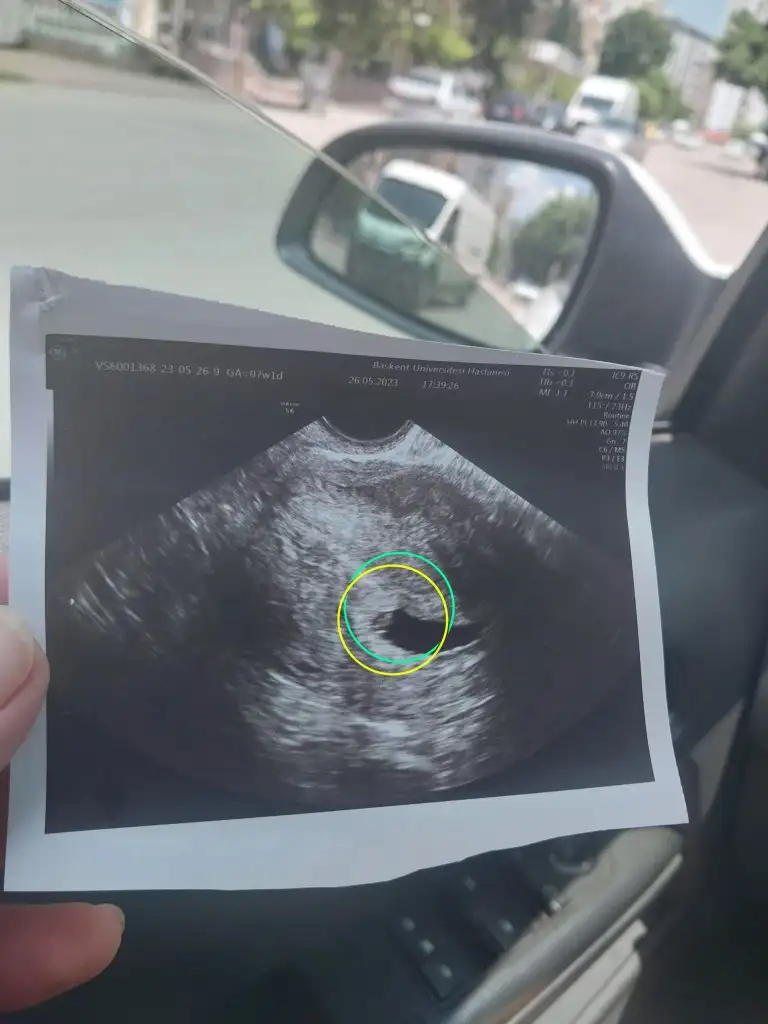

Salı günü 6+0 da dr gittim. Keseyi gördü

Vajinal baktı 16.8 mm dedi

Doktor salı güni gayet iyi sağlıklı kese de gördim dedi

Resmi de yüklüyorum